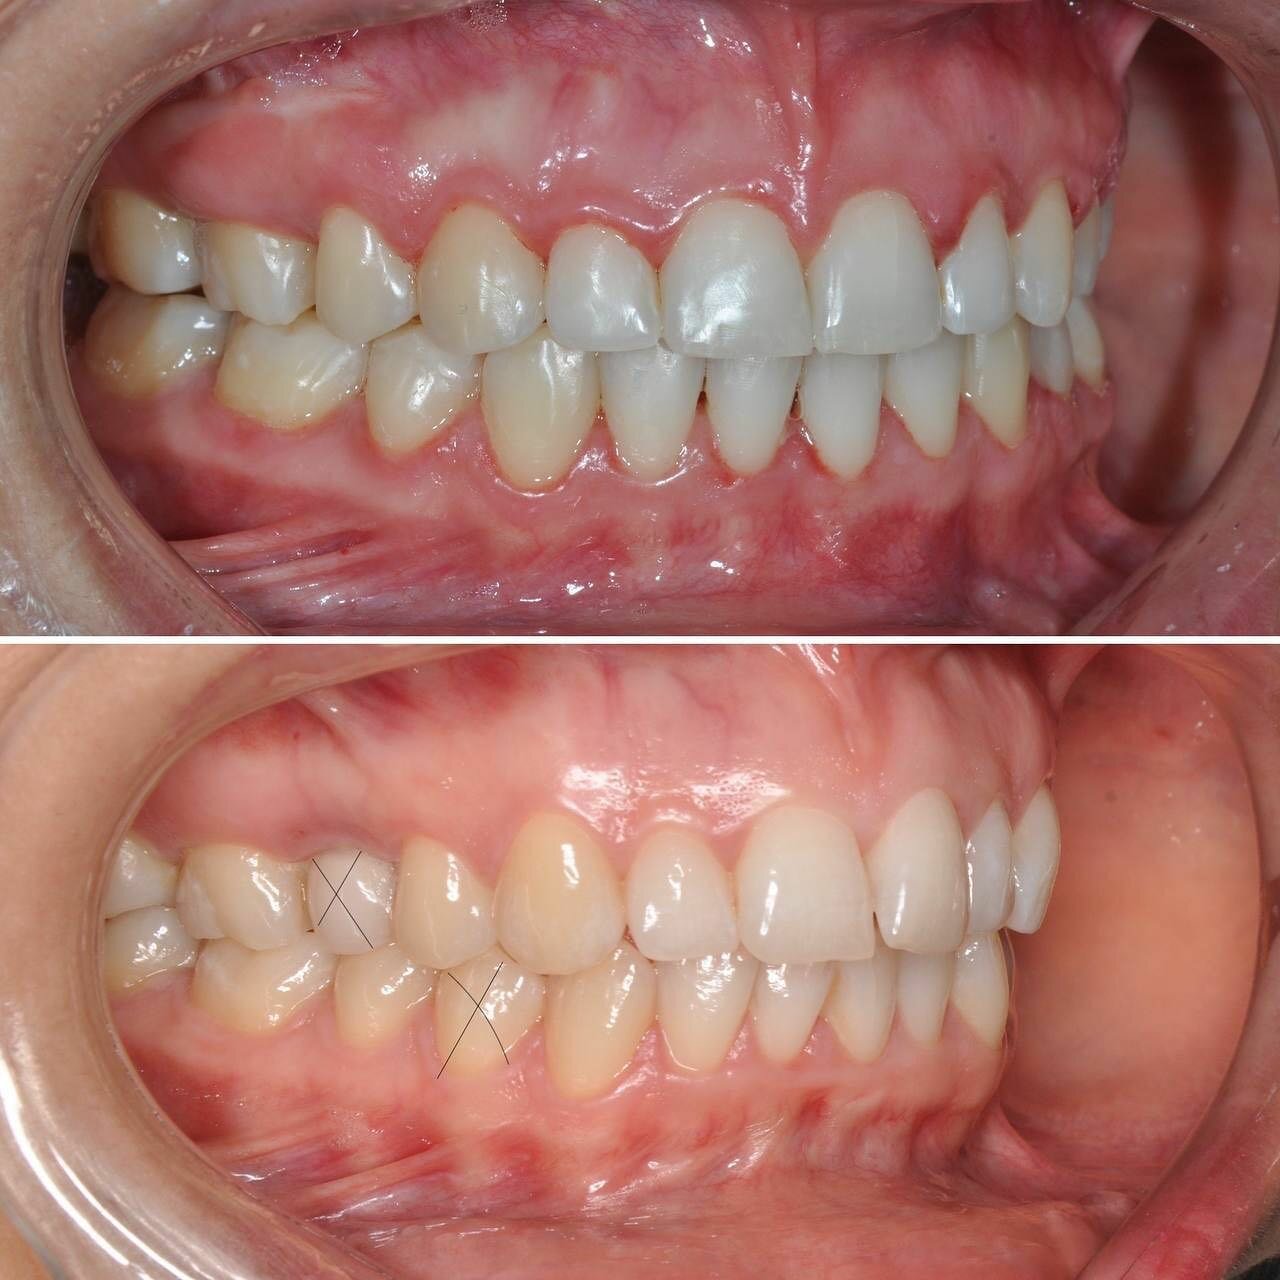

- ортодонтия

- брекеты

- Положительные впечатления от консультации и установки брекетов.

- Отрицательные последствия лечения (выпадение зубов, испорченный прикус).

Записывался на консультацию и дальнейшую установку брекетов для исправления прикуса. Впечатления на данный момент только положительные. Работа аккуратная, отношение вежливое, дополнительных услуг не навязывали.